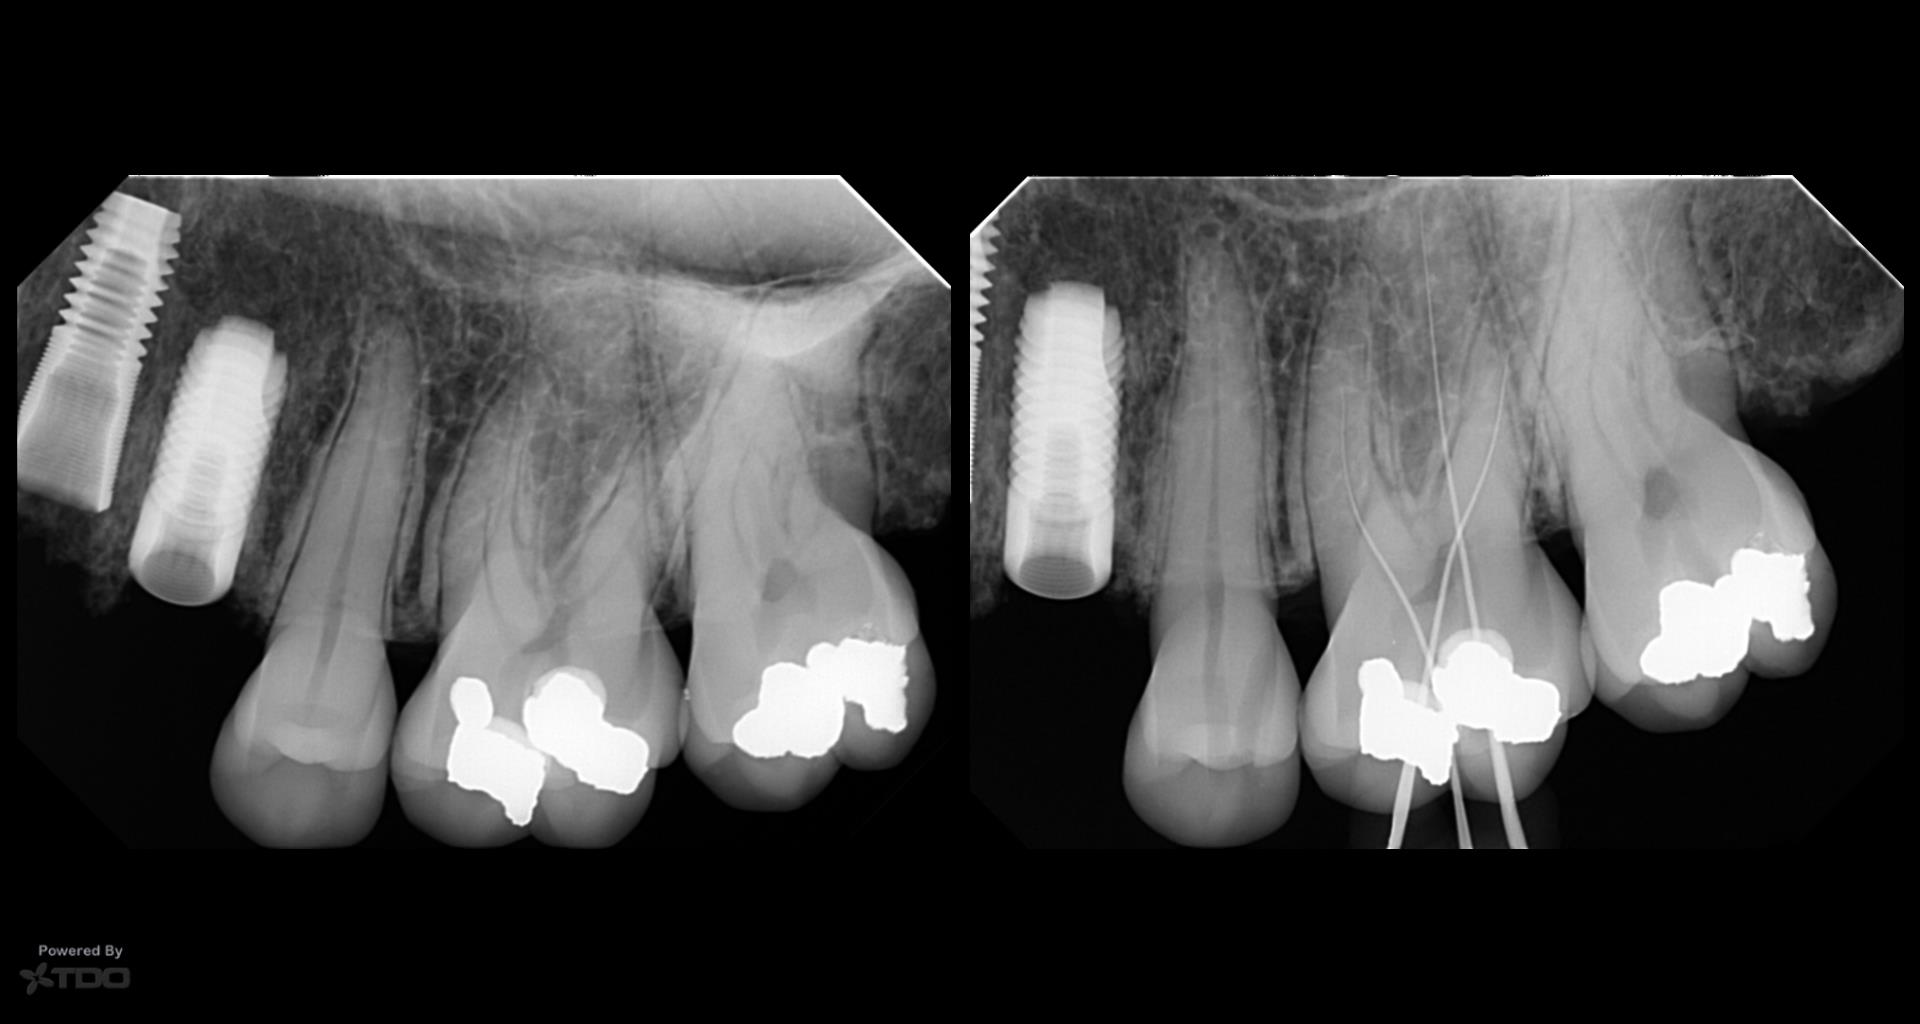

I have always wondered entry into the canal orifice requires precision but even more challenging is to be able to do it through 7-10 mm of dentin.

Any specific bur ? The angles of entry ?

Any slim ultrasonic to smoothen the entry point into dentin and the canal orifice ?

What kind of motions in this access referring to ergonomics ?